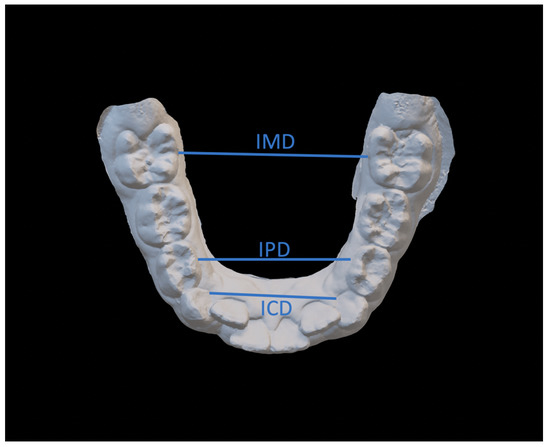

- Intercanine distance (ICD), calculated as the distance between the innermost lingual point of the gingival margin of the deciduous or permanent canines;

- Interpremolar distance (IPD), calculated as the distance between the innermost lingual point of the gingival margin of the first bicuspids or first deciduous molars;

- Intermolar distance (IMD), calculated as the distance between the points of intersection of the lingual sulcus with the cervical gingival margin of the first permanent molars;